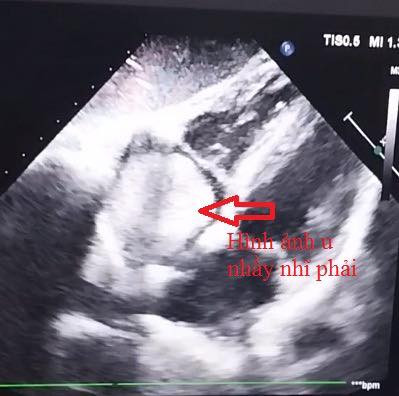

Kết quả siêu âm tim: U nhầy nhĩ phải kích thước 39x39x52mm đồng nhất, tròn đều, có cuốn, chiếm gần trọn nhĩ phải, u rất di động. Bệnh nhân có chỉ định phẫu thuật cấp cứu.

Ê-kíp phẫu thuật do BSCKII. Lâm Việt Triều, Trưởng khoa Phẫu thuật tim thực hiện ngay trong đêm, kết quả ghi nhận khối u có cuốn bám vào thành bên nhĩ phải, gần lỗ đổ tĩnh mạch chủ dưới, kích thước 50x40x30mm, mật độ u bở, nhiều múi, van ba lá hở do dãn vòng van. Tiến hành lấy trọn u kèm cuống, tái tạo một phần thành bên nhĩ phải, sửa van ba lá. Phẫu thuật thành công kết thúc vào lúc 03 giờ sáng.